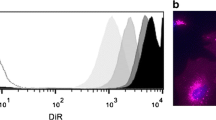

The mean fluorescence score for all evaluated regions of interest in all PMMA sections for viable bone was 4.56 (SD ± 0.79) indicating a strong to very strong fluorescence (AF group mean: 4.56, SD ± 0.5; TF group: mean: 4.56, SD ± 1.0; p > 0.05). The mean scoring of all evaluated regions of interest in all decalcified paraffin sections was clearly lower at 2.09 (SD ± 0.46) (AF group mean: 2.06, SD ± 0.43; TF group: mean: 2.13, SD ± 0.048; p > 0.05). No significant difference was observed with regard to the mean fluorescence between the auto- and the tetracycline-fluorescence groups (p > 0.05).

The mean fluorescence score for all evaluated regions of interest in all PMMA sections for necrotic bone was 1.22 (SD ± 0.42) indicating no fluorescence to very weak fluorescence (AF group mean: 1.11, SD ± 0.31; TF group: mean: 1.33, SD ± 0.47; p > 0.05). The mean scoring of all evaluated regions of interest in all decalcified paraffin sections was even lower at 1.0 (SD ± 0) (no fluorescence) (AF group mean: 1.0. SD ± 0; TF group: mean: 1.0, SD ± 0; p > 0.05). Again, no significant difference was noted with regard to the mean fluorescence between the auto- and the tetracycline-fluorescence groups (p > 0.05).

Histopathologically, a correlation was revealed between the structure of collagen and the fluorescence of the bone. In necrotic areas in which the arrangement and structure of collagen had changed, fluorescence decreased and disappeared. In viable bone in which the collagen remained unchanged, bright fluorescence was observed. In addition to that of the collagen, fluorescence was noted in cell-filled bone lacunae. Therefore, in areas of necrosis (empty bone lacunae), fluorescence was faint (Fig. 5). The correlation between collagen and fluorescence was determined by using a POL filter, which enabled collagen structures to be clearly depicted.

In the second part of the study, an evaluation was performed on both non-decalcified and decalcified histological preparations to determine whether the auto-fluorescence was mineral-dependent as assumed for tetracycline-fluorescence. As shown in the results of the semi-quantitative analysis, the decalcification of the sections decreased overall fluorescence. This is in line with the collagen-dependent fluorescence hypothesis. On decalcification, the stability and order of the collagen structure are destroyed, and therefore, the major fluorescence fades in paraffin sections. The remaining fluorescence is attributable to the bone cells (which contribute less brightness). In areas of necrosis with empty bone lacunae, no fluorescence can be detected at all.